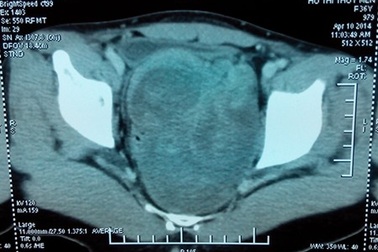

Lào Cai: Mổ thành công u nang buồng trứng nặng gần 6 kgBệnh viện Đa khoa Thị xã Sa Pa (Lào Cai) vừa mổ thành công lấy ra 2 khối u lớn, gồm một bọc nước và một khối u hỗn hợp, tổng gần 6 kg cho một nữ bệnh nhân 35 tuổi.